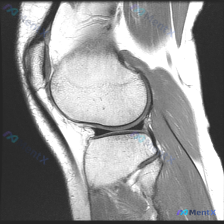

病例读片讨论:怀疑软骨异常,单张MRI却没发现问题,该怎么办? 这是一份膝关节矢状位T1加权MRI读片需求,核心疑问是排查软骨异常,我整理了完整的分析思路分享给大家。 一、影像基础信息 本次读片仅提供单张膝关节矢状位T1加权MRI图像: - T1序列中,骨髓脂肪呈高信号,液体、皮质骨、半月板等致密组...